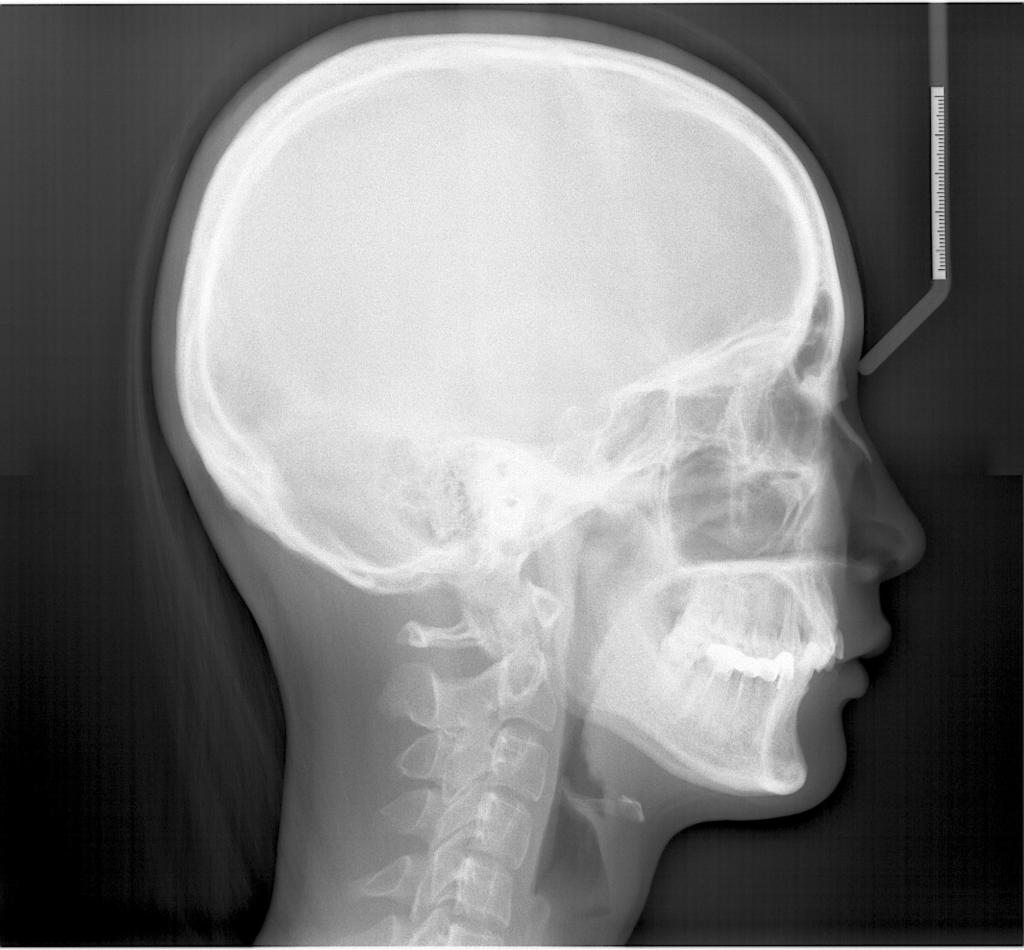

常规开展:数字化根尖片/横断牙合片、数字化口腔曲面体层片、头影测量侧位/正位片、手腕骨片、颅颌面CBCT、牙齿CBCT的检查以及涎腺造影、窦道 瘘管造影。

头影测量侧位/正位片